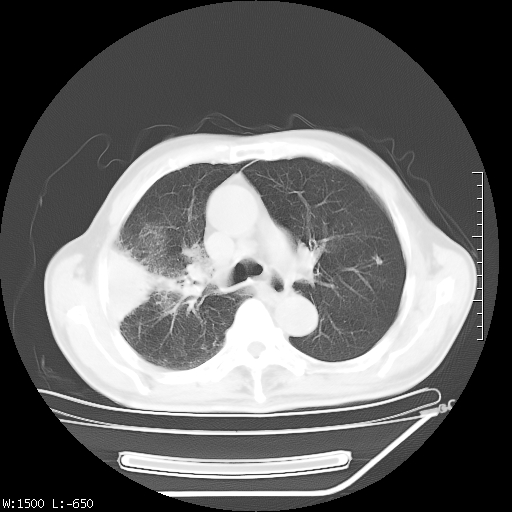

标题: CT23994:男、72、咳嗽、气短两月余,近来消瘦。 [打印本页]

标题: CT23994:男、72、咳嗽、气短两月余,近来消瘦。

右上肺实变,与胸膜关系密切,右肺容积缩小,隆突下淋巴结增大,考虑1 肺结核 2 肺癌

tb可能性大(双肺均可见片状密度增高灶,其内可见低密度空洞)。

右上肺大片状密度增高影,与胸膜关系密切,内见低密度透亮影,胸膜下可见三角形不张影,左下肺沿支气管走形结节影,纵膈内淋巴结显示。考虑结核并疤痕性不张可能性大,建议穿刺活检,排除肺泡癌。